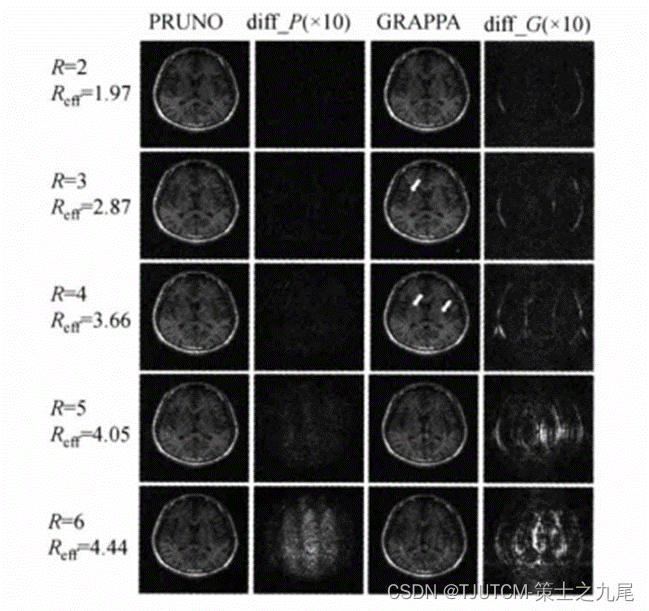

九、PRUNO重建算法

GRAPPA重建在低加速因子能产生很好的图像质量,而加速因子很高时其性能显著退化,除非强加大数目的自校准行(ACS)。而PRUTO是迭代K空间数据驱动pMRI重建算法,比GRAPPA更灵活。

在PRUNO中,数据校准和图像重建化为线性代数问题,迭代共轭梯度算法有效地用于解重建方程,得到的图像质量比GRAPPA更高,而要求的ACS行并不很多,尤其在高加速因子更具优势。

所用加速因子R=2-6,为便于比较差像夸大了10倍,ACS数据也包括在内导致Reff<R。对于GRAPPA,在R=3-4时伪影已经明显可见;而对于PRUNO,只要R<6(Reff<4),图像质量都不错,而且误差(aliasing)分布均匀。